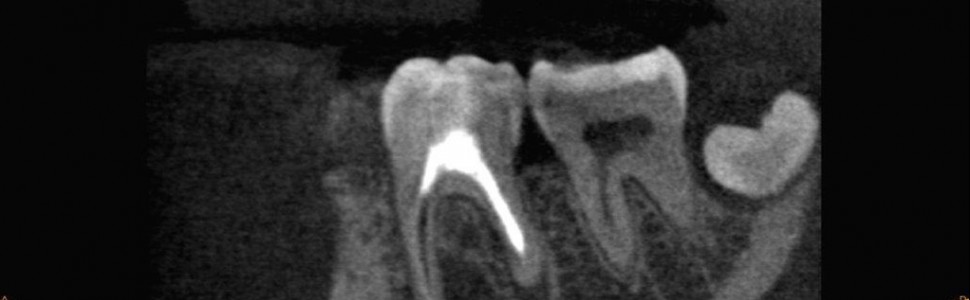

Wieloseansowe leczenie endodontyczne – opis dwóch przypadków

Współcześnie uważa się, że leczenie endodontyczne w przeważającej liczbie przypadków należy przeprowadzić metodą jednoseansową. Praca z mikroskopem, aktywacja płynów płuczących ultradźwiękami, użycie lasera czy szeroka oferta narzędzi endodontycznych i systemów usprawniają i skracają leczenie. Istnieją jednak sytuacje niezależne od operatora, kiedy zarówno stan miejscowy, np. nieuzyskanie suchości w kanale, jak i inne schorzenia pacjenta w postaci dysfunkcji stawów skroniowo-żuchwowych czy odcinka szyjnego kręgosłupa, wymuszają zastosowanie leczenia dwu- lub wieloseansowego. W niniejszej pracy przedstawiono opis dwóch przypadków wieloseansowego powtórnego leczenia endodontycznego.

Nowadays, it is believed that in most cases endodontic treatment should be performed in a single session. Working with a microscope, activation of rinsing fluids with ultrasound, the use of a laser, and a wide range of endodontic tools and systems improve and shorten the treatment. However, there are situations beyond the operator’s control when both the local condition, e.g. failure to achieve dryness in the canal, and other patient’s diseases such as dysfunction of the temporomandibular joints or cervical spine require the use of two- or multi-session treatment. This study describes two cases of multi-session endodontic retreatment.